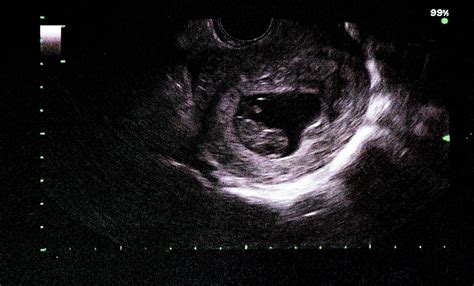

• 9 week baby ultrasound